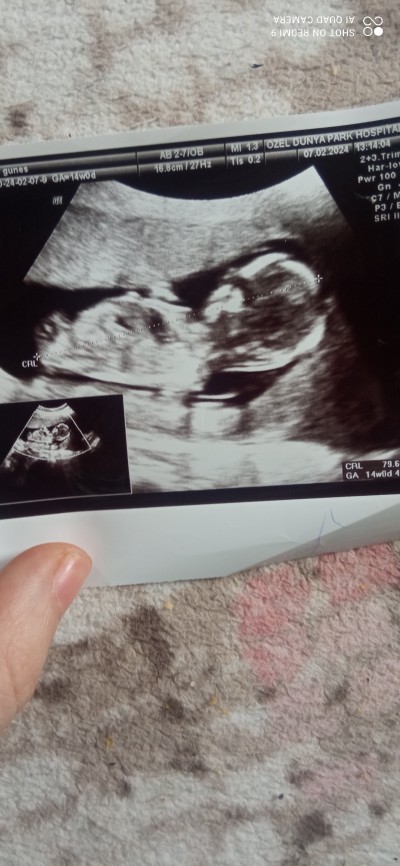

image

Oncelikle sağlıklı olmsasi kizimda oglumda var

Kız bence :)

Kız gibi duruyor

Kız bebek bence Dr birşey demedi mi çok küçük değil bebek

Doktor kiz gibi dedi yanilabilirim dedi sonra 16 haftaya kadr yanilma payı var dedi benimde iste merk

Bana da kız gibi geldi sağlıkla kucağına al cnm